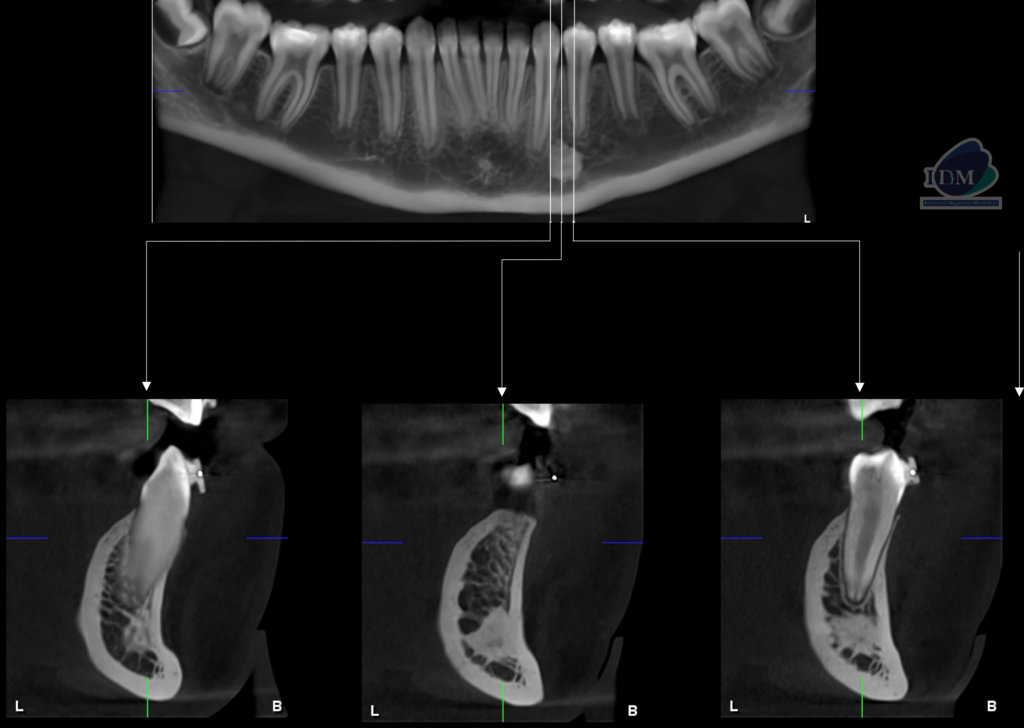

En la radiografía panorámica (Figura 1), se aprecia imagen radiopaca proyectada en cuerpo mandibular izquierdo, de limites definidos y forma irregular, que se extiende en sentido cefálico caudal desde nivel apical de pieza 33 hasta cortical superior del conducto dentario inferior.

Radiografia Panorámica